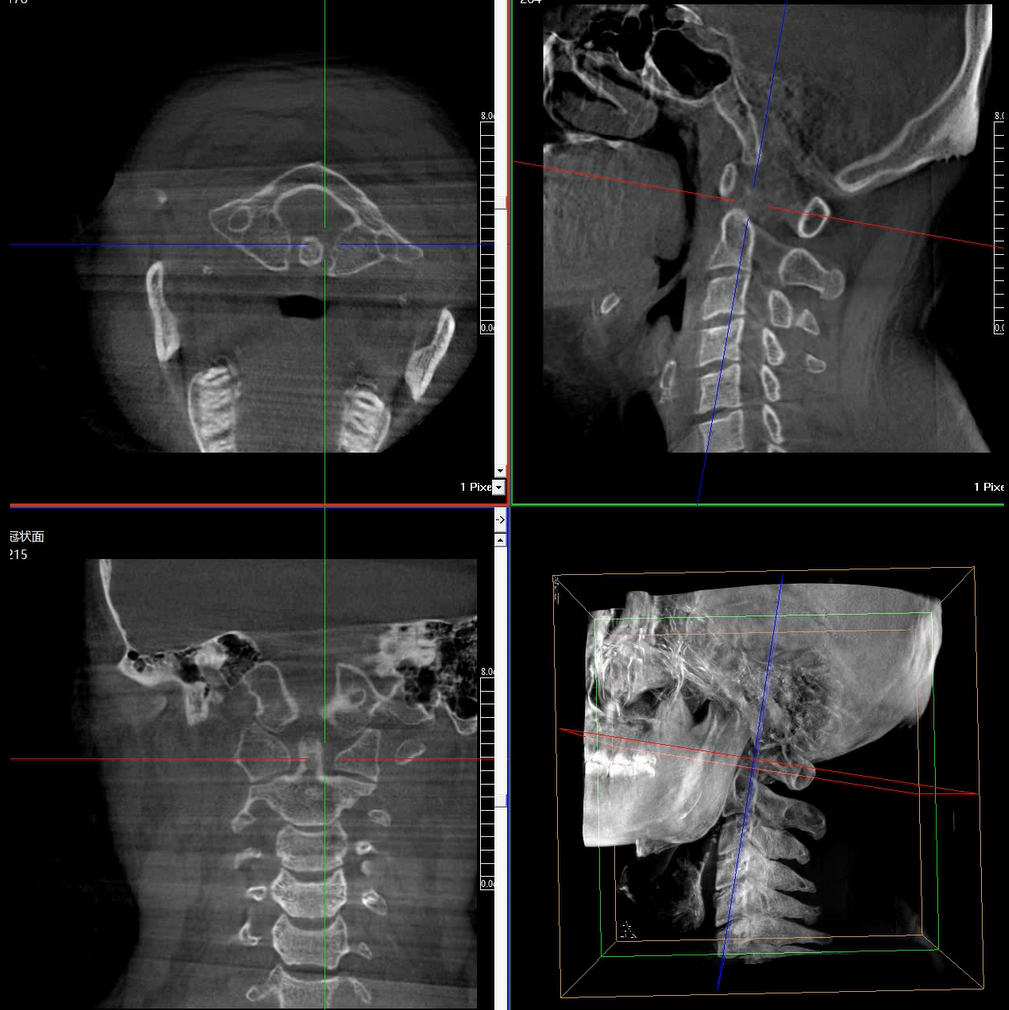

術(shù)中三維成像和橫斷面圖像提供多角度的手術(shù)診斷信息,輔助醫(yī)生進(jìn)行術(shù)中評(píng)估判斷,諸如骨折復(fù)位情況和內(nèi)植入螺釘?shù)某叽绾臀恢?,輔助手術(shù)更好地完成。

提供更大的術(shù)中三維成像視野,采集更多圖像信息,可一次拍全全段頸椎、全段腰椎、七節(jié)胸椎、雙側(cè)骶髂關(guān)節(jié)、股骨頭及單側(cè)盆骨。